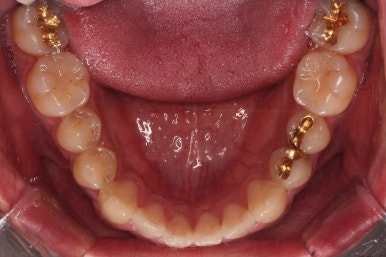

부산교정 장치를 부착했습니다.

이번에 선택하신 장치는 자가결찰 세라믹 장치에요. 스스로 철사를 묶는(결찰) 뚜껑이 달린(자가) 세라믹 성분의 장치인데요.

이번 환자분은 엠파워 클리어라고 하는 장치를 사용했으며 흔히 아신느 클리피씨와 동일한 계열의 장치입니다.

잇몸뼈에 미니스크류라고 하는 아주 작은 임플란트를 식립하고요.

미니스크류를 이용해서 뒤로 당겨주게 됩니다.